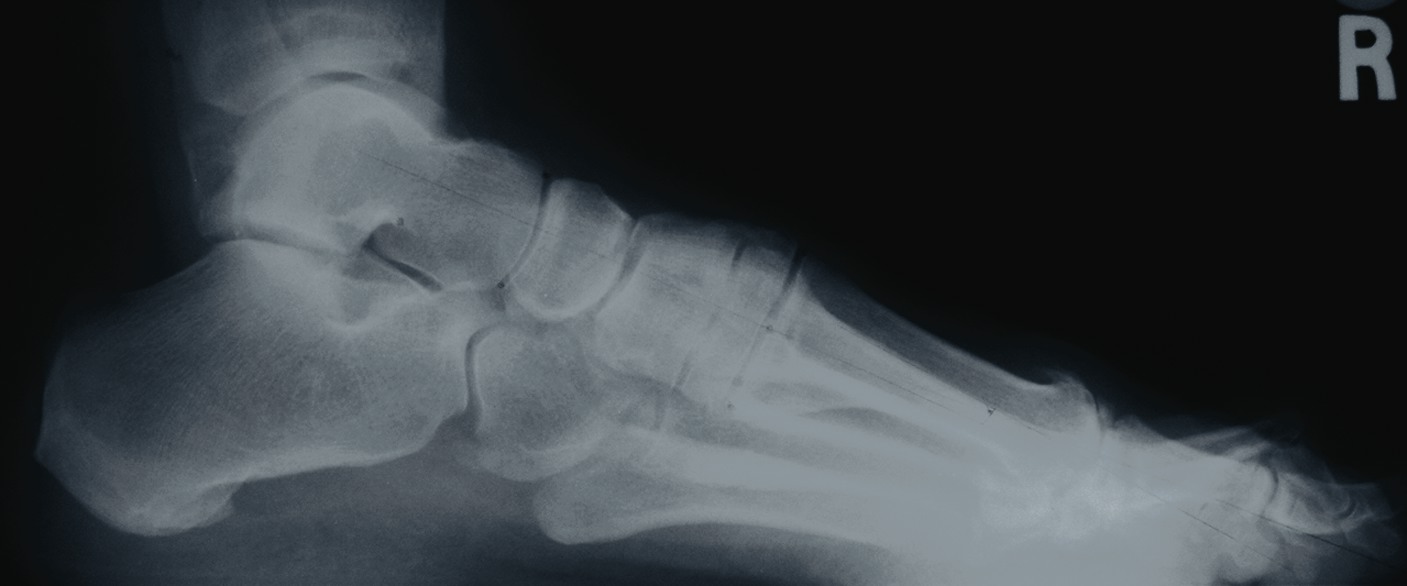

One should place the patient into a supine position and utilize a tourniquet. Evaluate post-anesthesia assessment of the first MPJ range of motion. Manually distract the first MPJ and plantarflex the first metatarsal. Dorsiflex the hallux to determine the obtainable first MPJ range of motion and evaluate for crepitus. If there is first ray hypermobility and no crepitus, one may be able to salvage the first MPJ by translating the first ray plantarly and stabilizing the medial column. Initially, surgeons should address contributing global pathology. Then proceed to the first ray and make a dorsomedial skin incision spanning the first MPJ. Retract the neurovascular structures. Make a longitudinal incision to bone, spanning the distal one-third of the first metatarsal and proximal one-half of the proximal phalanx. Evaluate the adjacent cartilage and make a critical decision to preserve or destroy the joint. It is important to realize that evaluation of cartilage quantity and quality via direct intraoperative visualization weighs heavily upon the final decision to perform a joint preservation or destructive procedure. One should strongly consider joint destructive procedures if greater than 30 percent of the dorsal portion of the first metatarsal head presents as grade III to grade IV chrondromalacia. One must independently evaluate grade III and IV chrondromalacia and osteochondral defects in the remaining 70 percent of the metatarsal head. Small cartilage lesions may yield themselves to debridement, drilling or OATS procedures whereas large cartilage defects will likely result in arthrodesis. If the joint is salvageable and one identifies first metatarsocuneiform hypermobility, perform a cheilectomy and a subsequent, sagittal Lapidus procedure. If one identifies hypermobility or posttraumatic first metatarsal angular pathology, correct it after completing the first MPJ soft tissue and osteophyte debridement. If one decides to perform arthrodesis on the joint, debride identified osteophytes, loose bodies, synovitis and scar tissue. Denude the adjacent cartilaginous surfaces to the healthy level of bleeding bone via curettage or via convex distal and concave proximal reamers. Fenestrate the adjacent bone surfaces with a 1.0- or 1.5-mm drill bit. Temporarily fixate the hallux by utilizing two K-wires in the desired position. The position should be approximately 20 to 30 degrees dorsiflexed in relation to the first metatarsal declination; abducted and parallel to the second digit; and with the nail void of frontal plane varus or valgus rotation. Obtain an AP radiograph to evaluate the bony apposition and alignment of the proposed first MPJ arthrodesis. Also obtain a lateral radiograph with the foot loaded in order to evaluate the hallux and its relationship to the first ray. After obtaining the desired position, utilize two fully threaded (3.5 or 4.0) crossing cortical screws for permanent fixation. Place the first screw from proximal medial to distal lateral and place the second screw from distal medial to proximal lateral across the first MPJ. Ensure the screws do not cross at the level of the joint. Use a 3.5-mm burr to create a dell in the cortical bone where the head of the screws engage the bone as Manloli and Hansen have described.48 After obtaining rigid internal fixation across the first MPJ, utilize a shear strain autograft (harvested via a percutaneous calcaneal grafting technique) at the arthrodesis site.57 Place the autograft in two troughs created by the 3.5-mm burr at the arthrodesis site. Use a bone mallet and tamp to provide a press fit.58